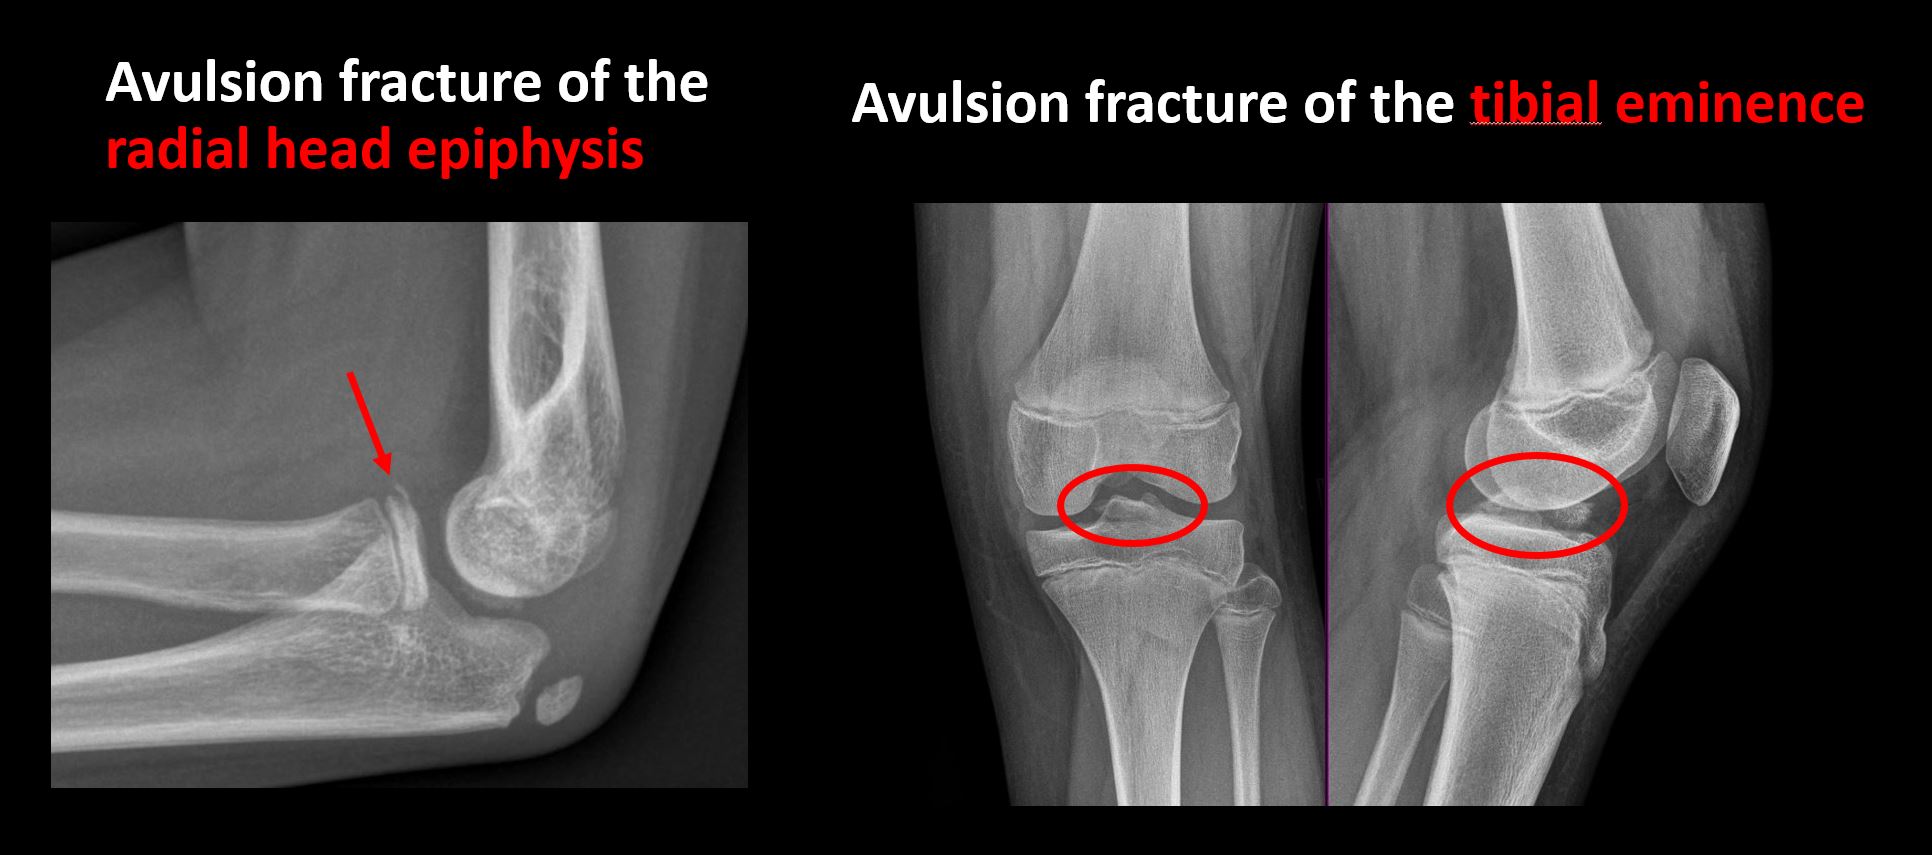

There is a displaced fragment which may be from avulsion by a tendon, ligament, or joint capsule or from a comminuted or other fracture. [Yes/No]

The apophysis, epicondyle, secondary ossification center, or accessory ossicle is displaced or otherwise abnormal (e.g. avulsed ASIS, medial epicondyle of the humerus, etc). [Yes/No]

The epiphysis or subchondral bone is fractured, interrupted, flattened, compressed, impacted, displaced, or otherwise abnormal. [Yes/No]